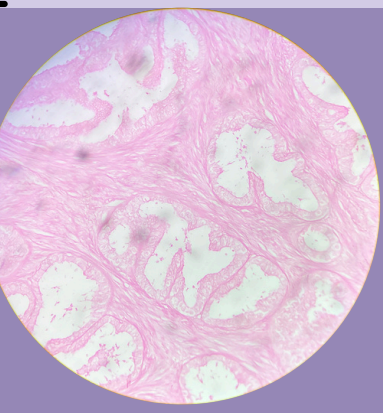

Fibroadenoma de mama:

Proliferación del estroma intralobular

Presencia de ductos comprimidos